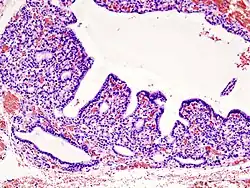

Involution - normal atrophy, e.g. thymus in adults, uterus in the older woman.